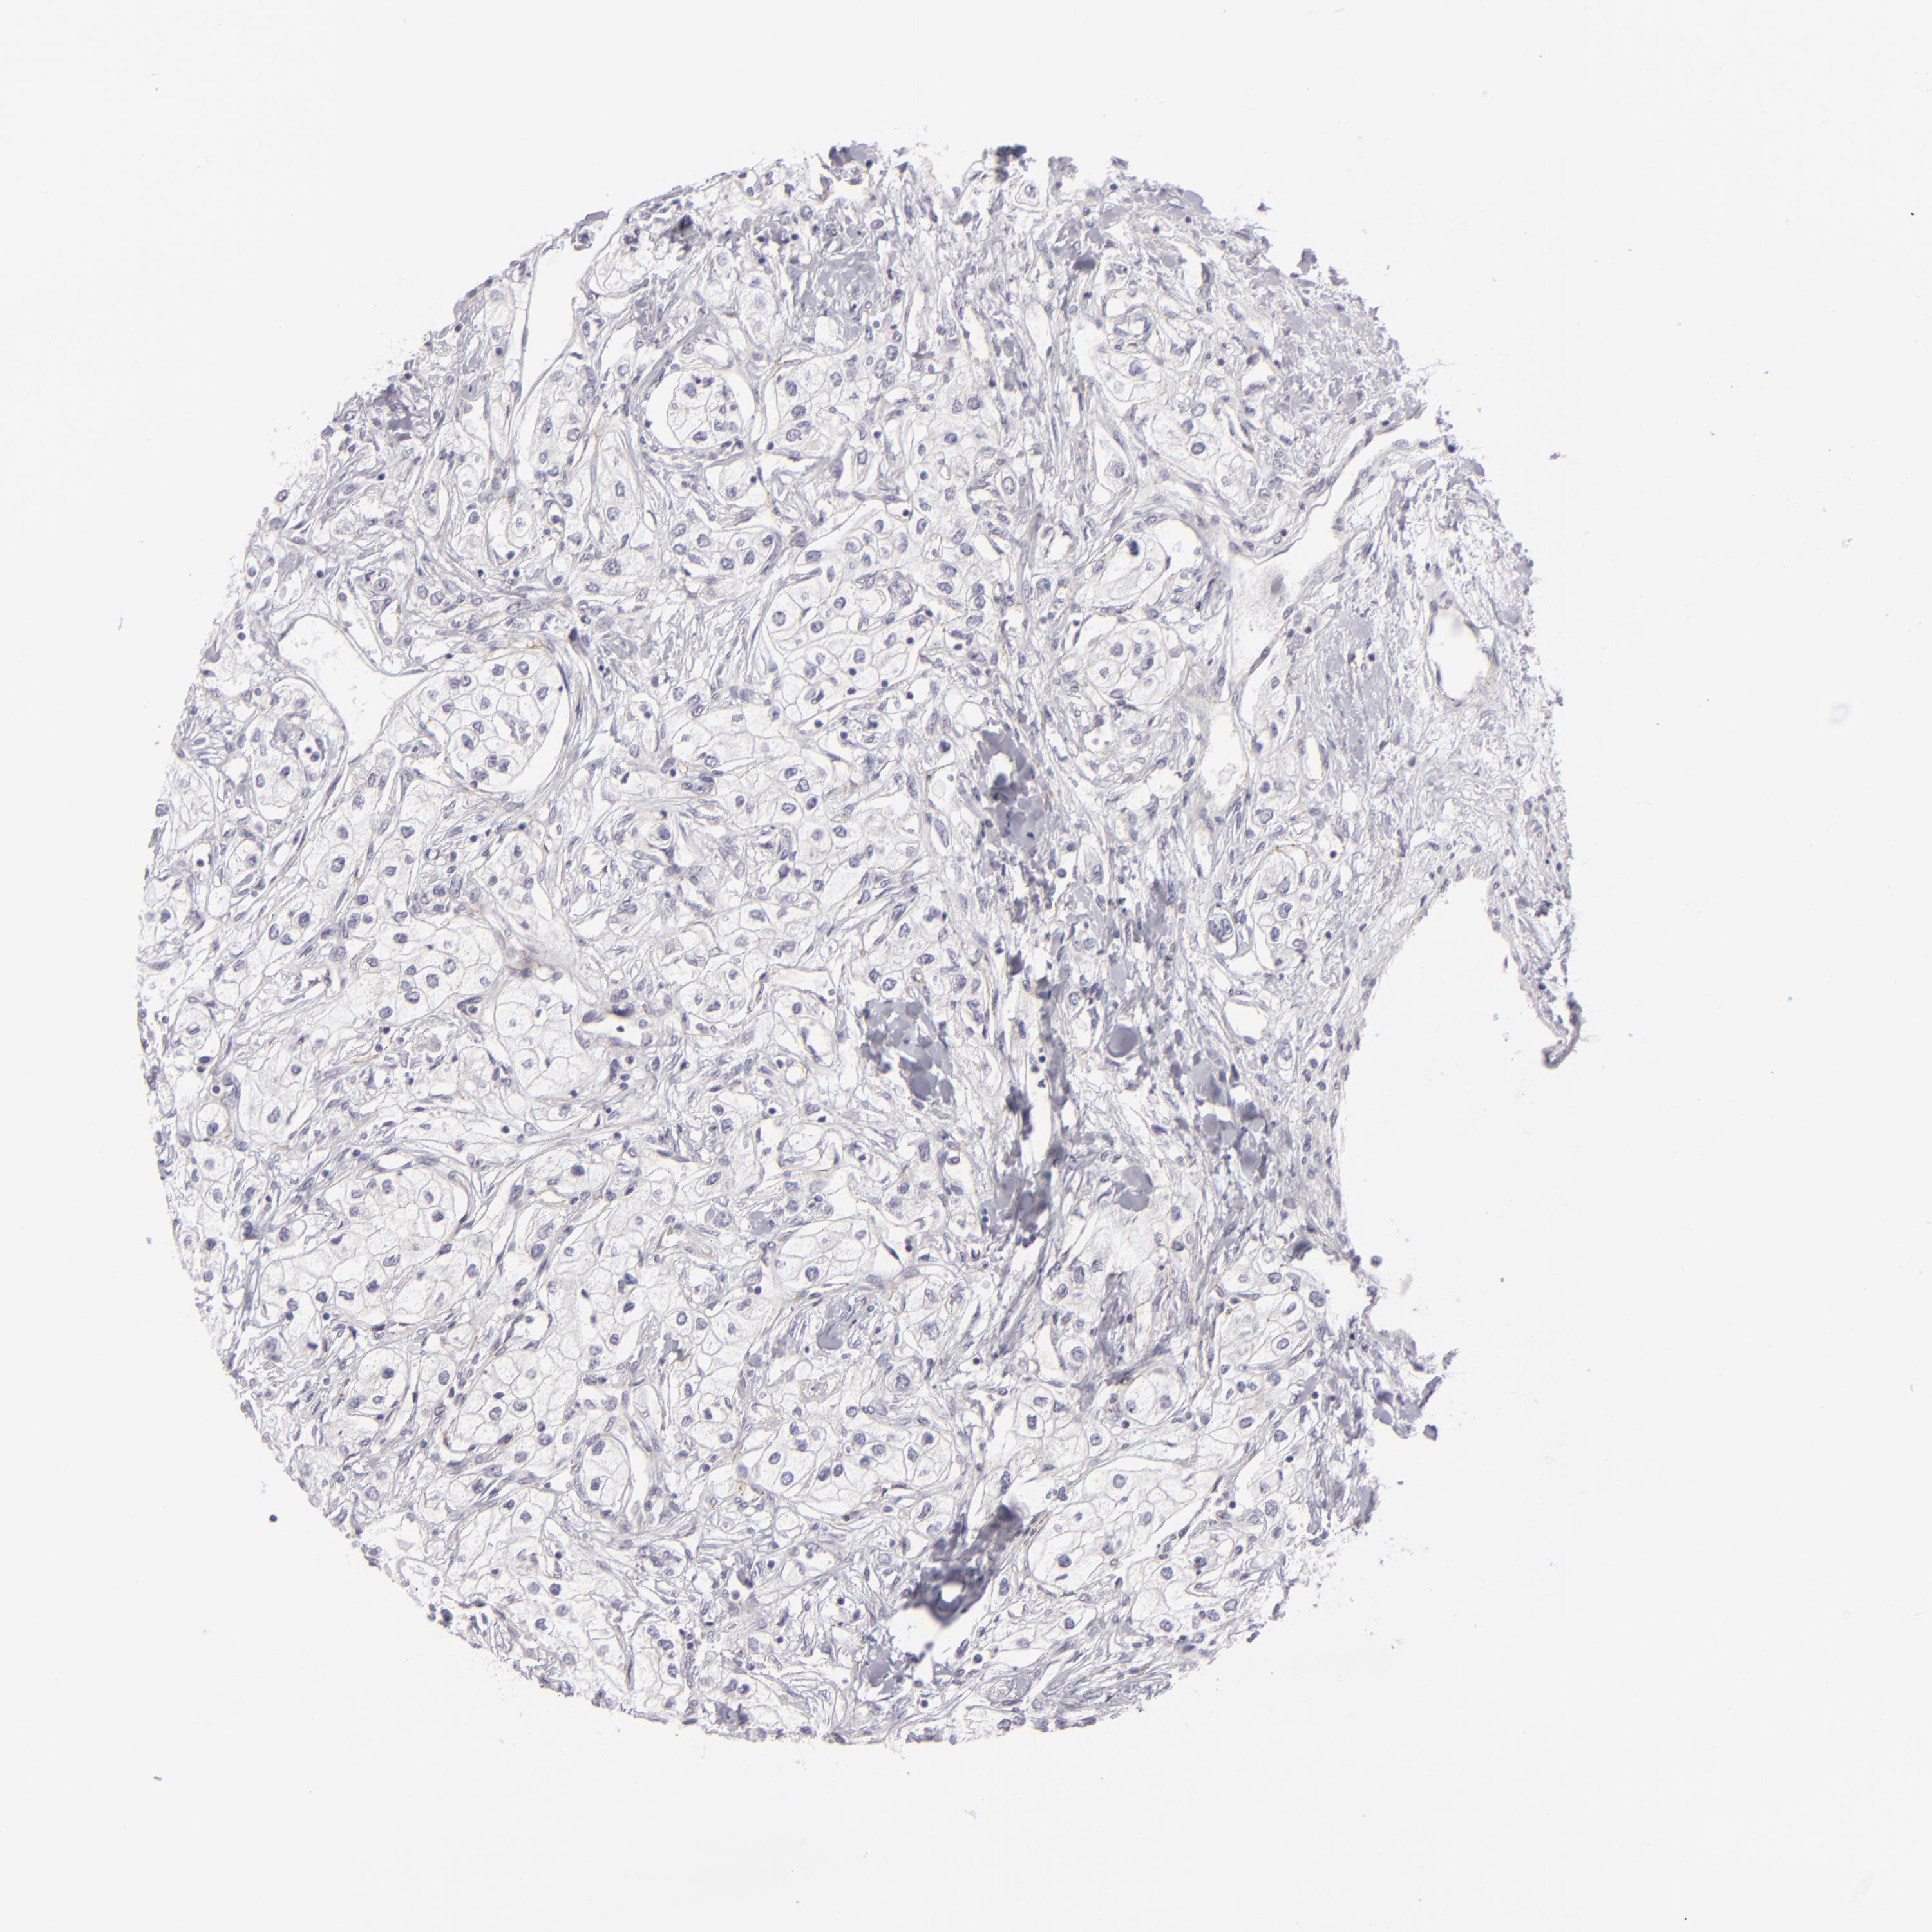

KIDNEY RENAL CLEAR CELL CARCINOMA (VALIDATION) - Interactive survival scatter ploti

The Survival Scatter plot shows the clinical status (i.e. dead or alive) for all individuals in the patient cohort, based on the same data that underlies the corresponding Kaplan-Meier plots. Patients that are alive at last time for follow-up are shown in blue and patients who have died during the study are shown in red.

The x-axis shows the expression levels (FPKM) of the investigated gene in the tumor tissue at the time of diagnosis. The y-axis shows the follow-up time after diagnosis (years). Both axes are complimented with kernel density curves demonstrating the data density over the axes. The top density plot shows the expression levels (FPKM) distribution among dead (red) and alive patients (blue). The right density plot shows the data density of the survived years of dead patients with high and low expression levels respectively, stratified using the cutoff indicated by the vertical dashed line through the Survival Scatter plot. This cutoff is automatically defined based on the FPKM cutoff that minimizes the p-score. The cutoff can be changed by dragging the vertical line or by entering a cutoff value in the square labeled "Current cut-off".

Under the Survival Scatter plot the p-score landscape (black curve; left axis) is shown together with dead median separation (red curve; right axis). Dead median separation is the difference in median mRNA expression between patients who have died with high and low expression, respectively. It is calculated as follows: median FPKM expression of dead patients with high expression - median FPKM expression of dead patients with low expression. This is intended to aid the user in visually exploring custom cutoffs and the associated p-scores and dead median separation.

Individual patient data is displayed and can be filtered by clicking on one or more of the category buttons on the top of the page. Categories describing expression level and patient information include: high, low, alive, dead, female, male and tumor stages. The scale of the x-axis can be toggled between linear and log-scale by clicking on the "x log" button. Mouse-over function shows TCGA ID, patient information and mRNA expression (FPKM) for each patient.

& Survival analysisi

Kaplan-Meier plots summarize results from analysis of correlation between mRNA expression level and patient survival. Patients were divided based on level of expression into one of the two groups "low" (under cut off) or "high" (over cut off). X-axis shows time for survival (years) and y-axis shows the probability of survival, where 1.0 corresponds to 100 percent.

JUP is validated prognostic, high expression is favorable in Kidney Renal Clear Cell Carcinoma (validation)

Best expression cut offi

Based on the FPKM value of each gene, patients were classified into two groups and association between prognosis (survival) and gene expression (FPKM) was examined. The best expression cut-off refers the FPKM value that yields maximal difference with regard to survival between the two groups at the lowest log-rank P-value. Best expression cut-off was selected based on survival analysis .

When clicking on this number, the vertical dashed line indicating cut-off, the interactive survival plot, and the Kaplan-Meier curve will be adjusted to show results based on the best expression cut-off.

: 90.21

TCGA RNA samplesi

RNA-seq data is reported as average FPKM (number Fragments Per Kilobase of exon per Million reads), generated by the The Cancer Genome Atlas (TCGA) .

Normal distribution across the dataset is visualized with box plots, shown as median and 25th and 75th percentiles. Points are displayed as outliers if they are above or below 1.5 times the interquartile range. FPKM values of the individual samples are presented next to the box plot.

Average pTPM 89.2

Number of samples 100